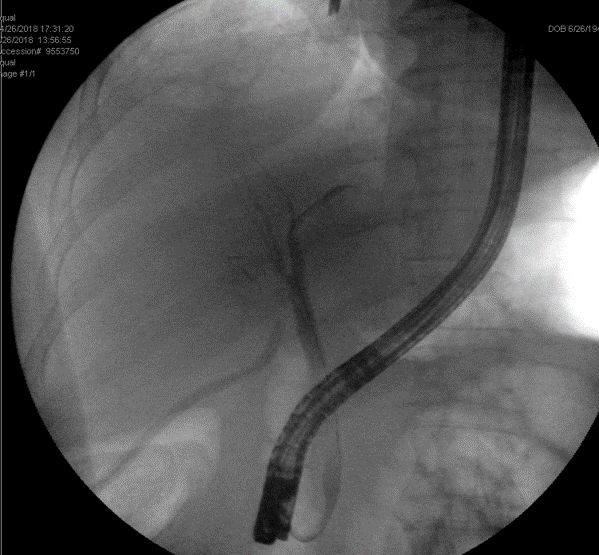

Subsequent tube checks to visualize the size of the biloma demonstrated backfilling of the CBD through a newly patent cystic duct at 3 months post-operatively (see figure 3). A PTBD was inserted into the posterior sectional duct with its tip lying in the hilum and the subhepatic pigtail drain was removed from under the liver (see figure 4).

Figure 3. Tube check cholangiogram through percutaneous pigtail drain into biloma in the gallbladder fossa demonstrates new patency of the cystic duct (thick arrow) and back-filling of the CBD out of the biloma (thin arrow).